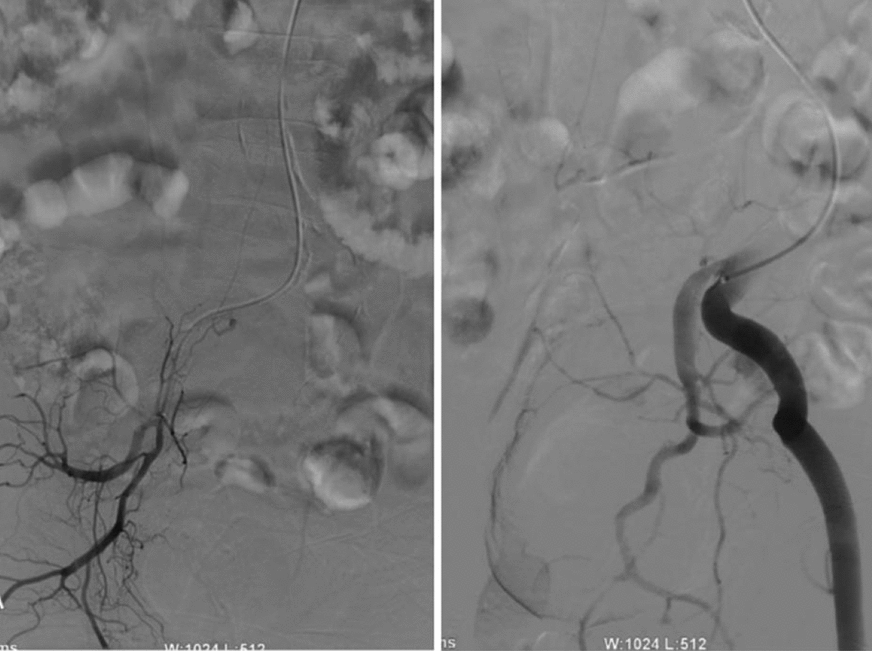

Case presentation: A 76-year-old Chinese male patient presented with numbness and weakness of the lower limbs that rapidly progressed to complete paralysis within 4 days. Patient was diagnosed with spinal dural arteriovenous fistula after magnetic resonance imaging and spinal vascular angiography, undergoing bilateral internal iliac artery embolization 2 weeks later, and started rehabilitation 40 days later but only received minimal improvement 1 year thereafter.